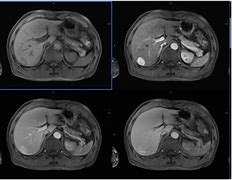

转移和扩散是肝癌的特征之一 , 因此肝癌可以转移 , 最常见的转移部位如下:

肺:约占转移瘤总数的76% 。 肺转移主要由小肿瘤血栓引起 。 大多数肺转移瘤体积小 , 直径很少超过LCM;临床表现主要包括干咳、胸痛、咯血、痰或咯血等 。 广泛转移时也可出现胸闷、气短等临床表现 , 肺转移的发生率在远处转移中最高 。

骨:约占转移瘤总数的11% , 在原发性肝癌中也很常见 。 转移部位包括脊椎骨、髂骨、髋骨、肋骨、胸骨、锁骨、颅骨等 , 其中大部分为胸椎和腰椎 。 临床表现主要为局部压痛和神经卡压症状 。 疼痛特征从间歇性逐渐变为持续性 , 表现为进行性加重 , 后期也可发生病理性骨折 。

颅内:肝癌可通过血液通道转移至大脑 , 临床表现主要为头痛、恶心、呕吐、肢体活动不良等神经定位症状和体征 。 淋巴结:肝癌也可转移至肝门、锁骨上、主动脉旁、胰腺、脾脏等部位的淋巴结 。 临床表现主要为无痛性淋巴结肿大 。 其他:肝癌也可移植到腹膜、膈肌、胸部等部位 , 主要表现为腹痛、血性腹水、胸腔积液等临床症状 。